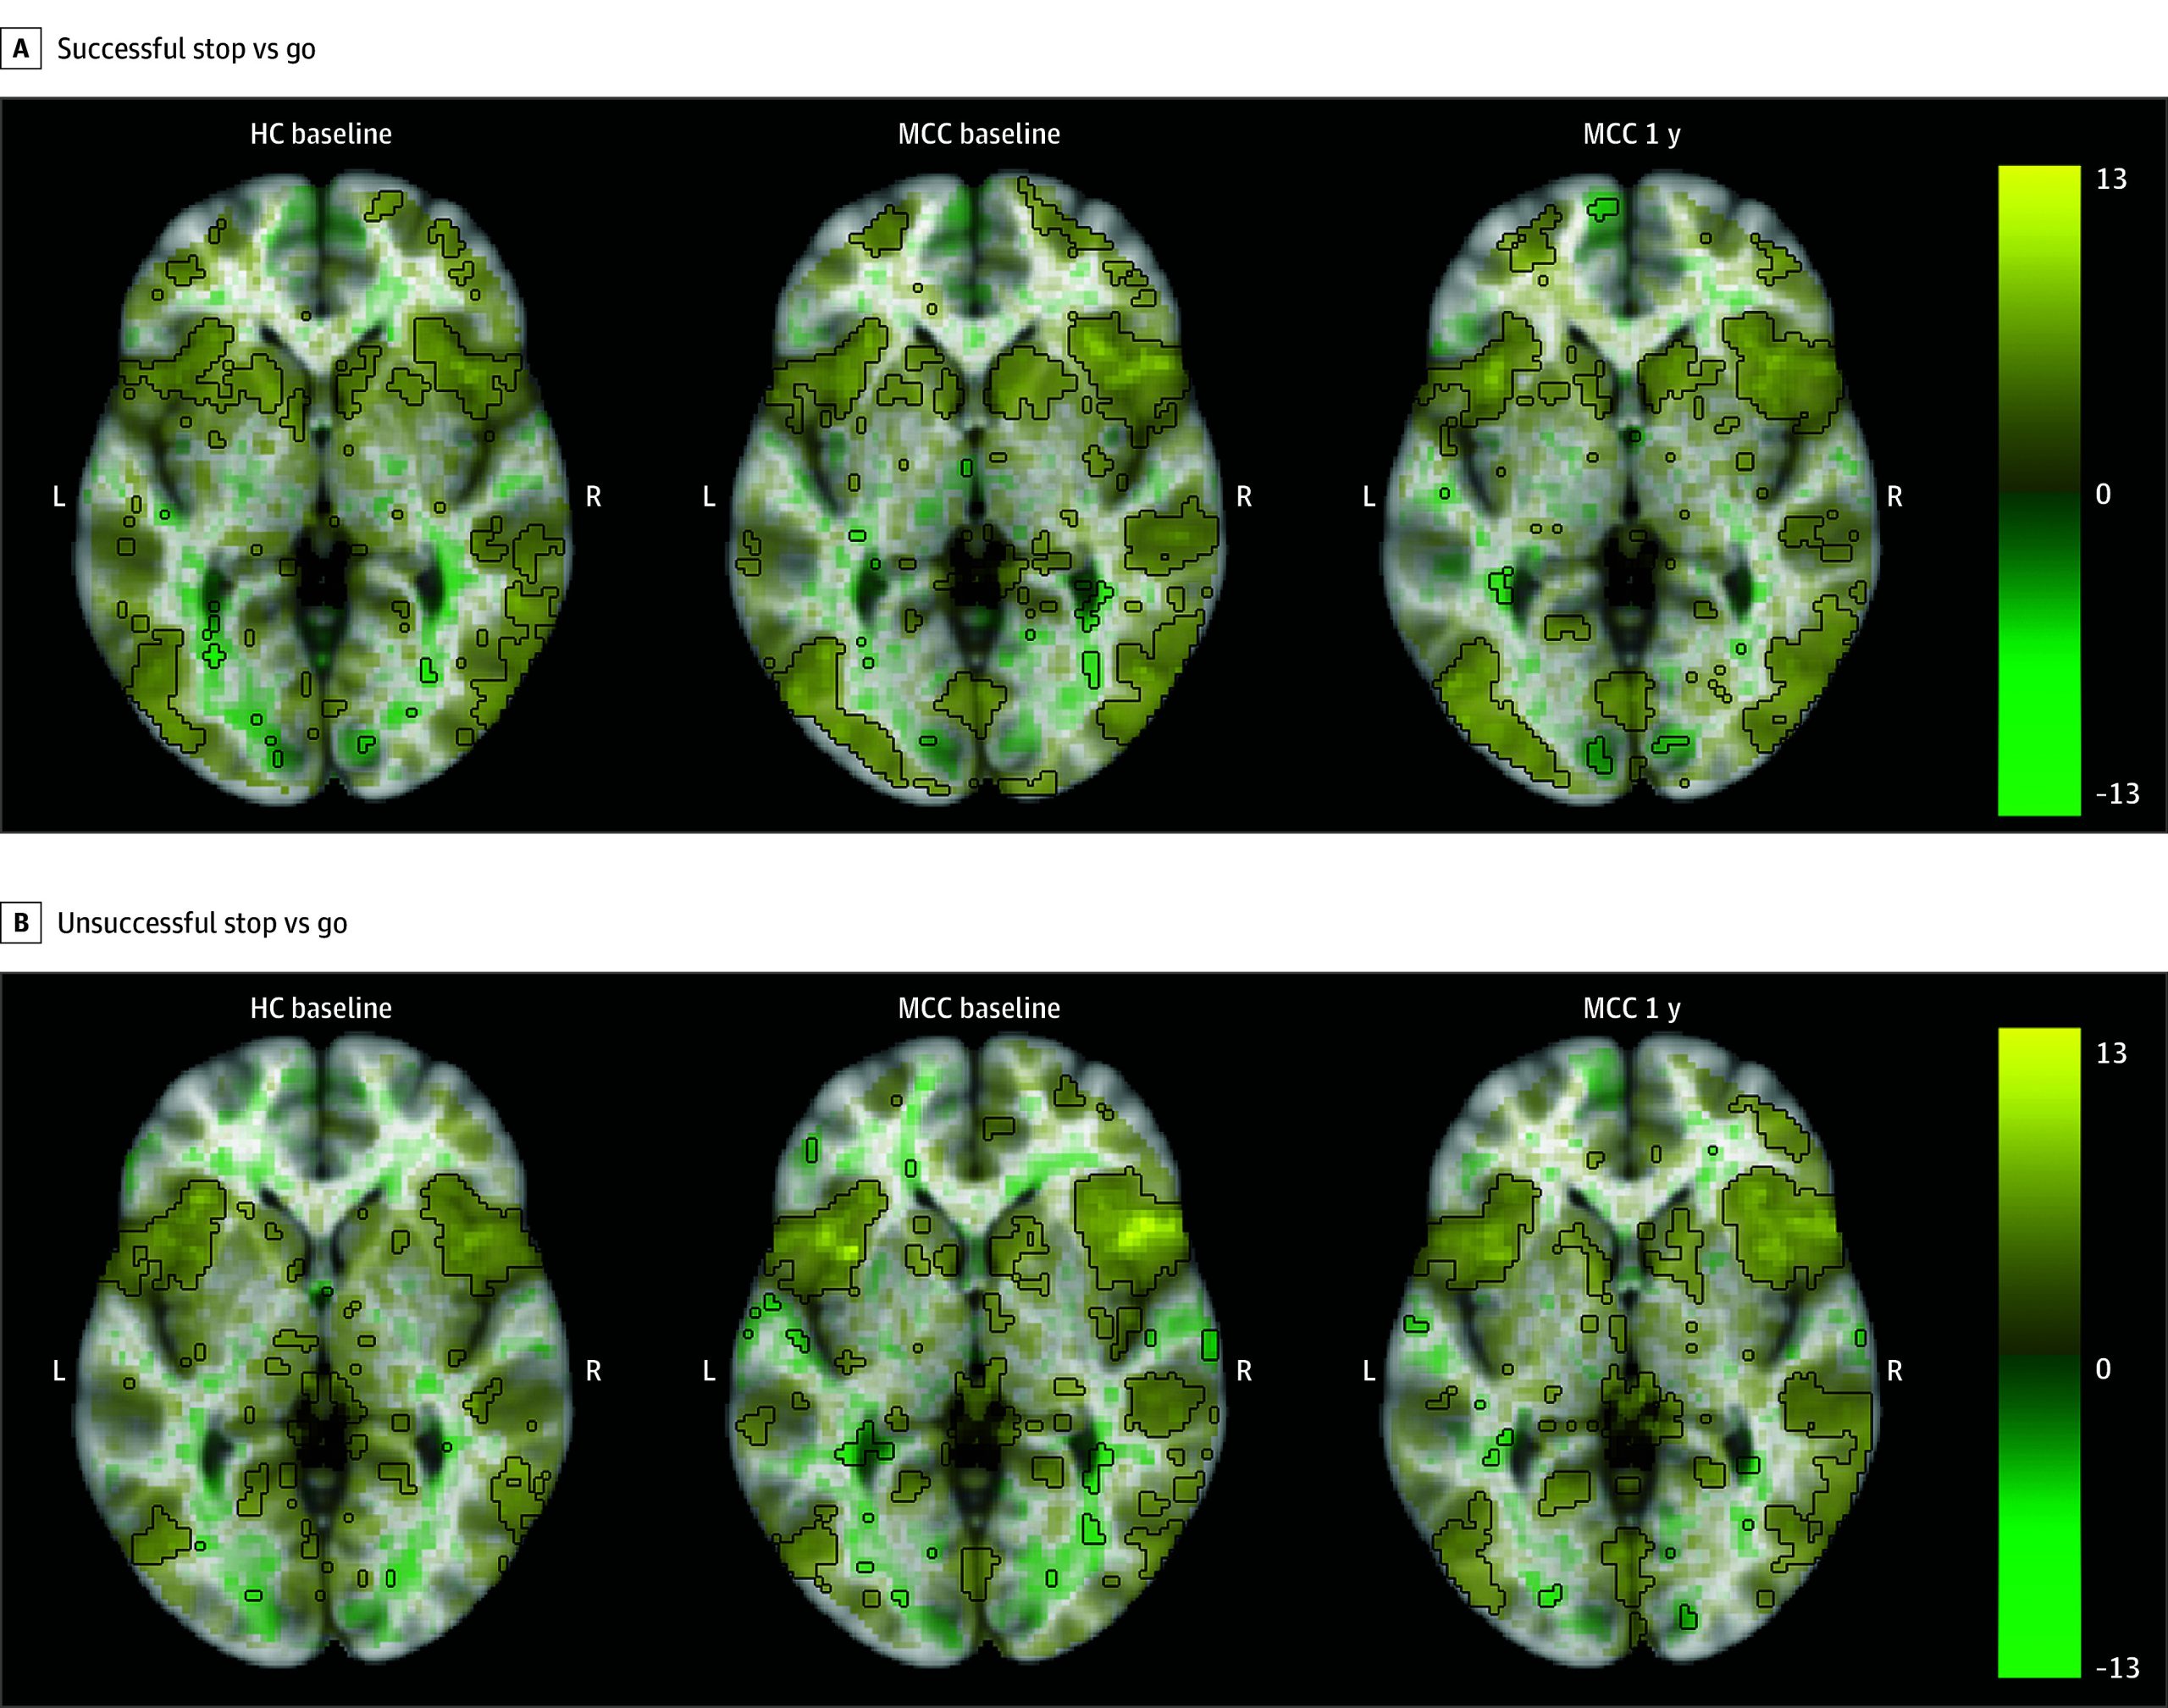

All groups showed activation in inhibitory control-related regions, including the right inferior frontal gyrus, frontal gyrus, and insula during the correct inhibition, incorrect inhibition, and successful inhibitory control contrasts (Figure 3; eAppendix 1 and eFigures 9-11 in Supplement 1). No differences in activation between the groups at baseline (25 HC participants and 40 MCC participants) or between the 2 time points of the MCC group (26 participants), and no associations of cannabis use frequency change with activation at 1 year for the MCC group were significant.